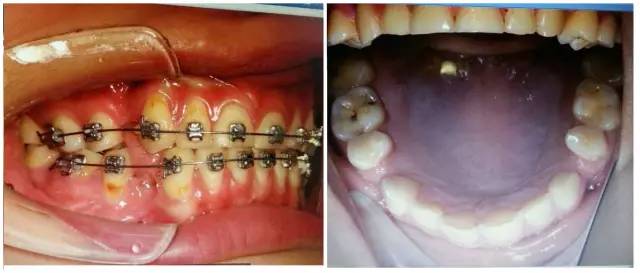

5.jpg

由上圖可知,患者全口牙齒磨耗較重,尖牙牙尖磨耗,無法起到引導和保護作用,上前牙牙根短,上中切牙腭側面邊緣嵴消失,

由此推斷:尖牙牙尖磨耗,患者在前伸(牙合)運動時,引導不足,前牙的接觸面過大,受力較大;患者在側方(牙合)運動時下前牙沒有了引導,會直接對側切牙造成撞擊;再加上前牙根較短,無法耐受,引起(牙合)創(chuàng)傷,繼發(fā)牙髓癥狀;失去尖牙保護(牙合),加重了牙齒的磨耗。